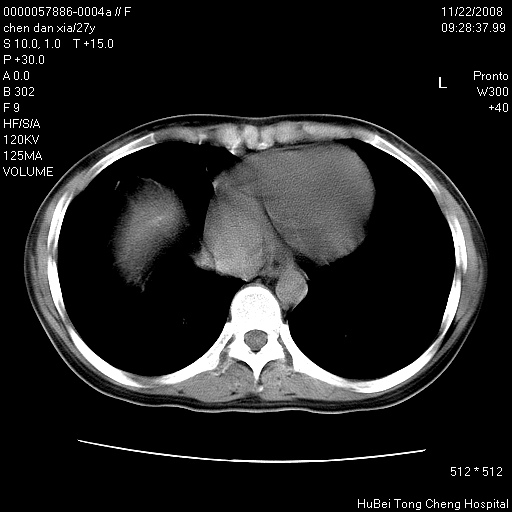

标题: CT16752:F,27Y。发热咳嗽20余天,伴盗汗。 [打印本页]

标题: CT16752:F,27Y。发热咳嗽20余天,伴盗汗。

考虑双肺粟粒性肺tb,右侧胸膜增厚.

气管前腔静脉后淋巴结肿大 右肺门纹理模糊

淋巴结核?

右下肺见片絮状影,两肺野内分布不均的小结节影,结核并肺内播散可能性大,建议结合实验室检查 .

右下肺纹理模糊;纵隔可见肿大淋巴节;右心缘旁结节,边缘光滑,纵隔窗病变范围较肺窗明显小,首先考虑右下肺结核,不排外淋巴瘤

下肺结节,结节内钙化,肺门纵隔淋巴肿大 结核可能性大

气管前腔静脉后淋巴结肿大 右肺门纹理模糊[br]淋巴结核?